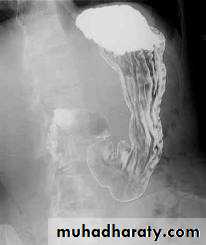

Barium meal Fluoroscopy + spot films Preparation

The Normal Anatomy of Stomach1- Shape.2-Size.3-Site.4-Anatomical parts.5-Mucosal pattern.

Normal Anatomy of DuodenumDuodenal cap.Duodenal loop